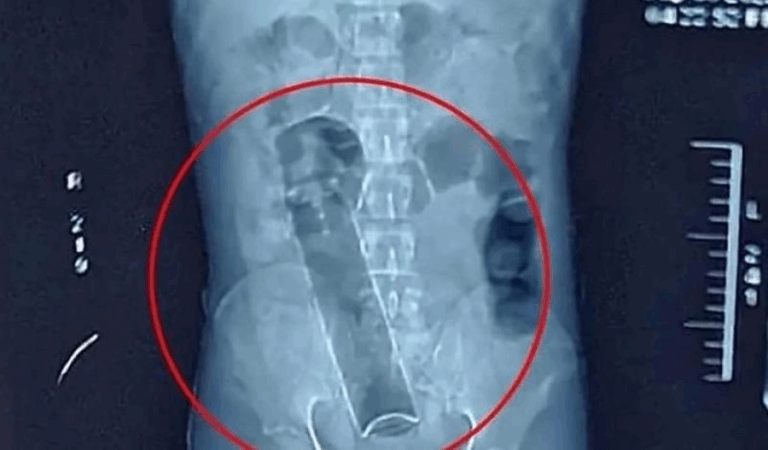

Homem dá entrada em hospital de Porto Velho com frasco de desodorante preso no reto e precisa passar por cirurgia

Um caso inusitado e delicado mobilizou equipes médicas do Hospital João Paulo